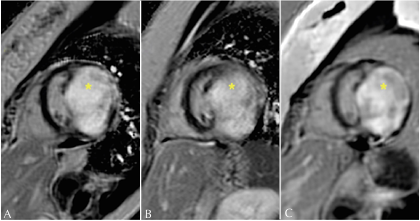

Figure 2: Short axis (A) and four-chamber (B-C), presenting intramyocardial mass (*) isointense in T1. 2016 (A), 2018 (B), and 2020 (C).